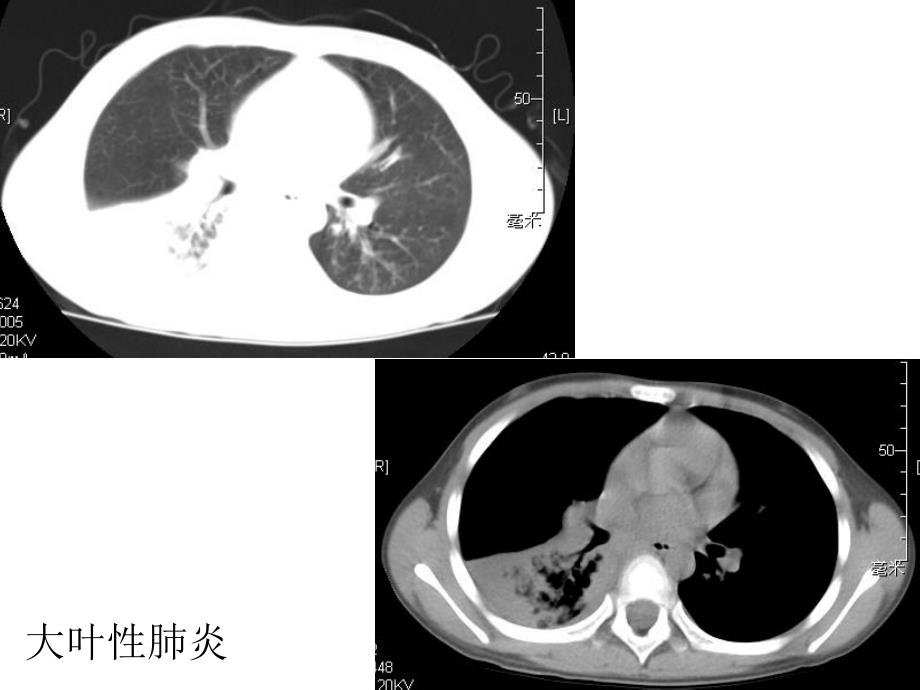

呼吸系统及纵隔呼吸系统及纵隔奇奇 叶叶大叶性肺炎 肺大疱 肺炎治疗后复查 慢性支气管炎、肺气肿 心包积液 支气管扩张 支气管扩张 支气管扩张病例1:鸽子肺CT:27088病例2少量胸腔积液的CT和MR周围型肺癌(小细胞癌)中心型肺癌正常上叶舌段支气管肺上沟癌MR:050668肺挫伤肋骨骨折,胸腔积液,肺不张皮下积气升主动脉瘤 主动脉夹层